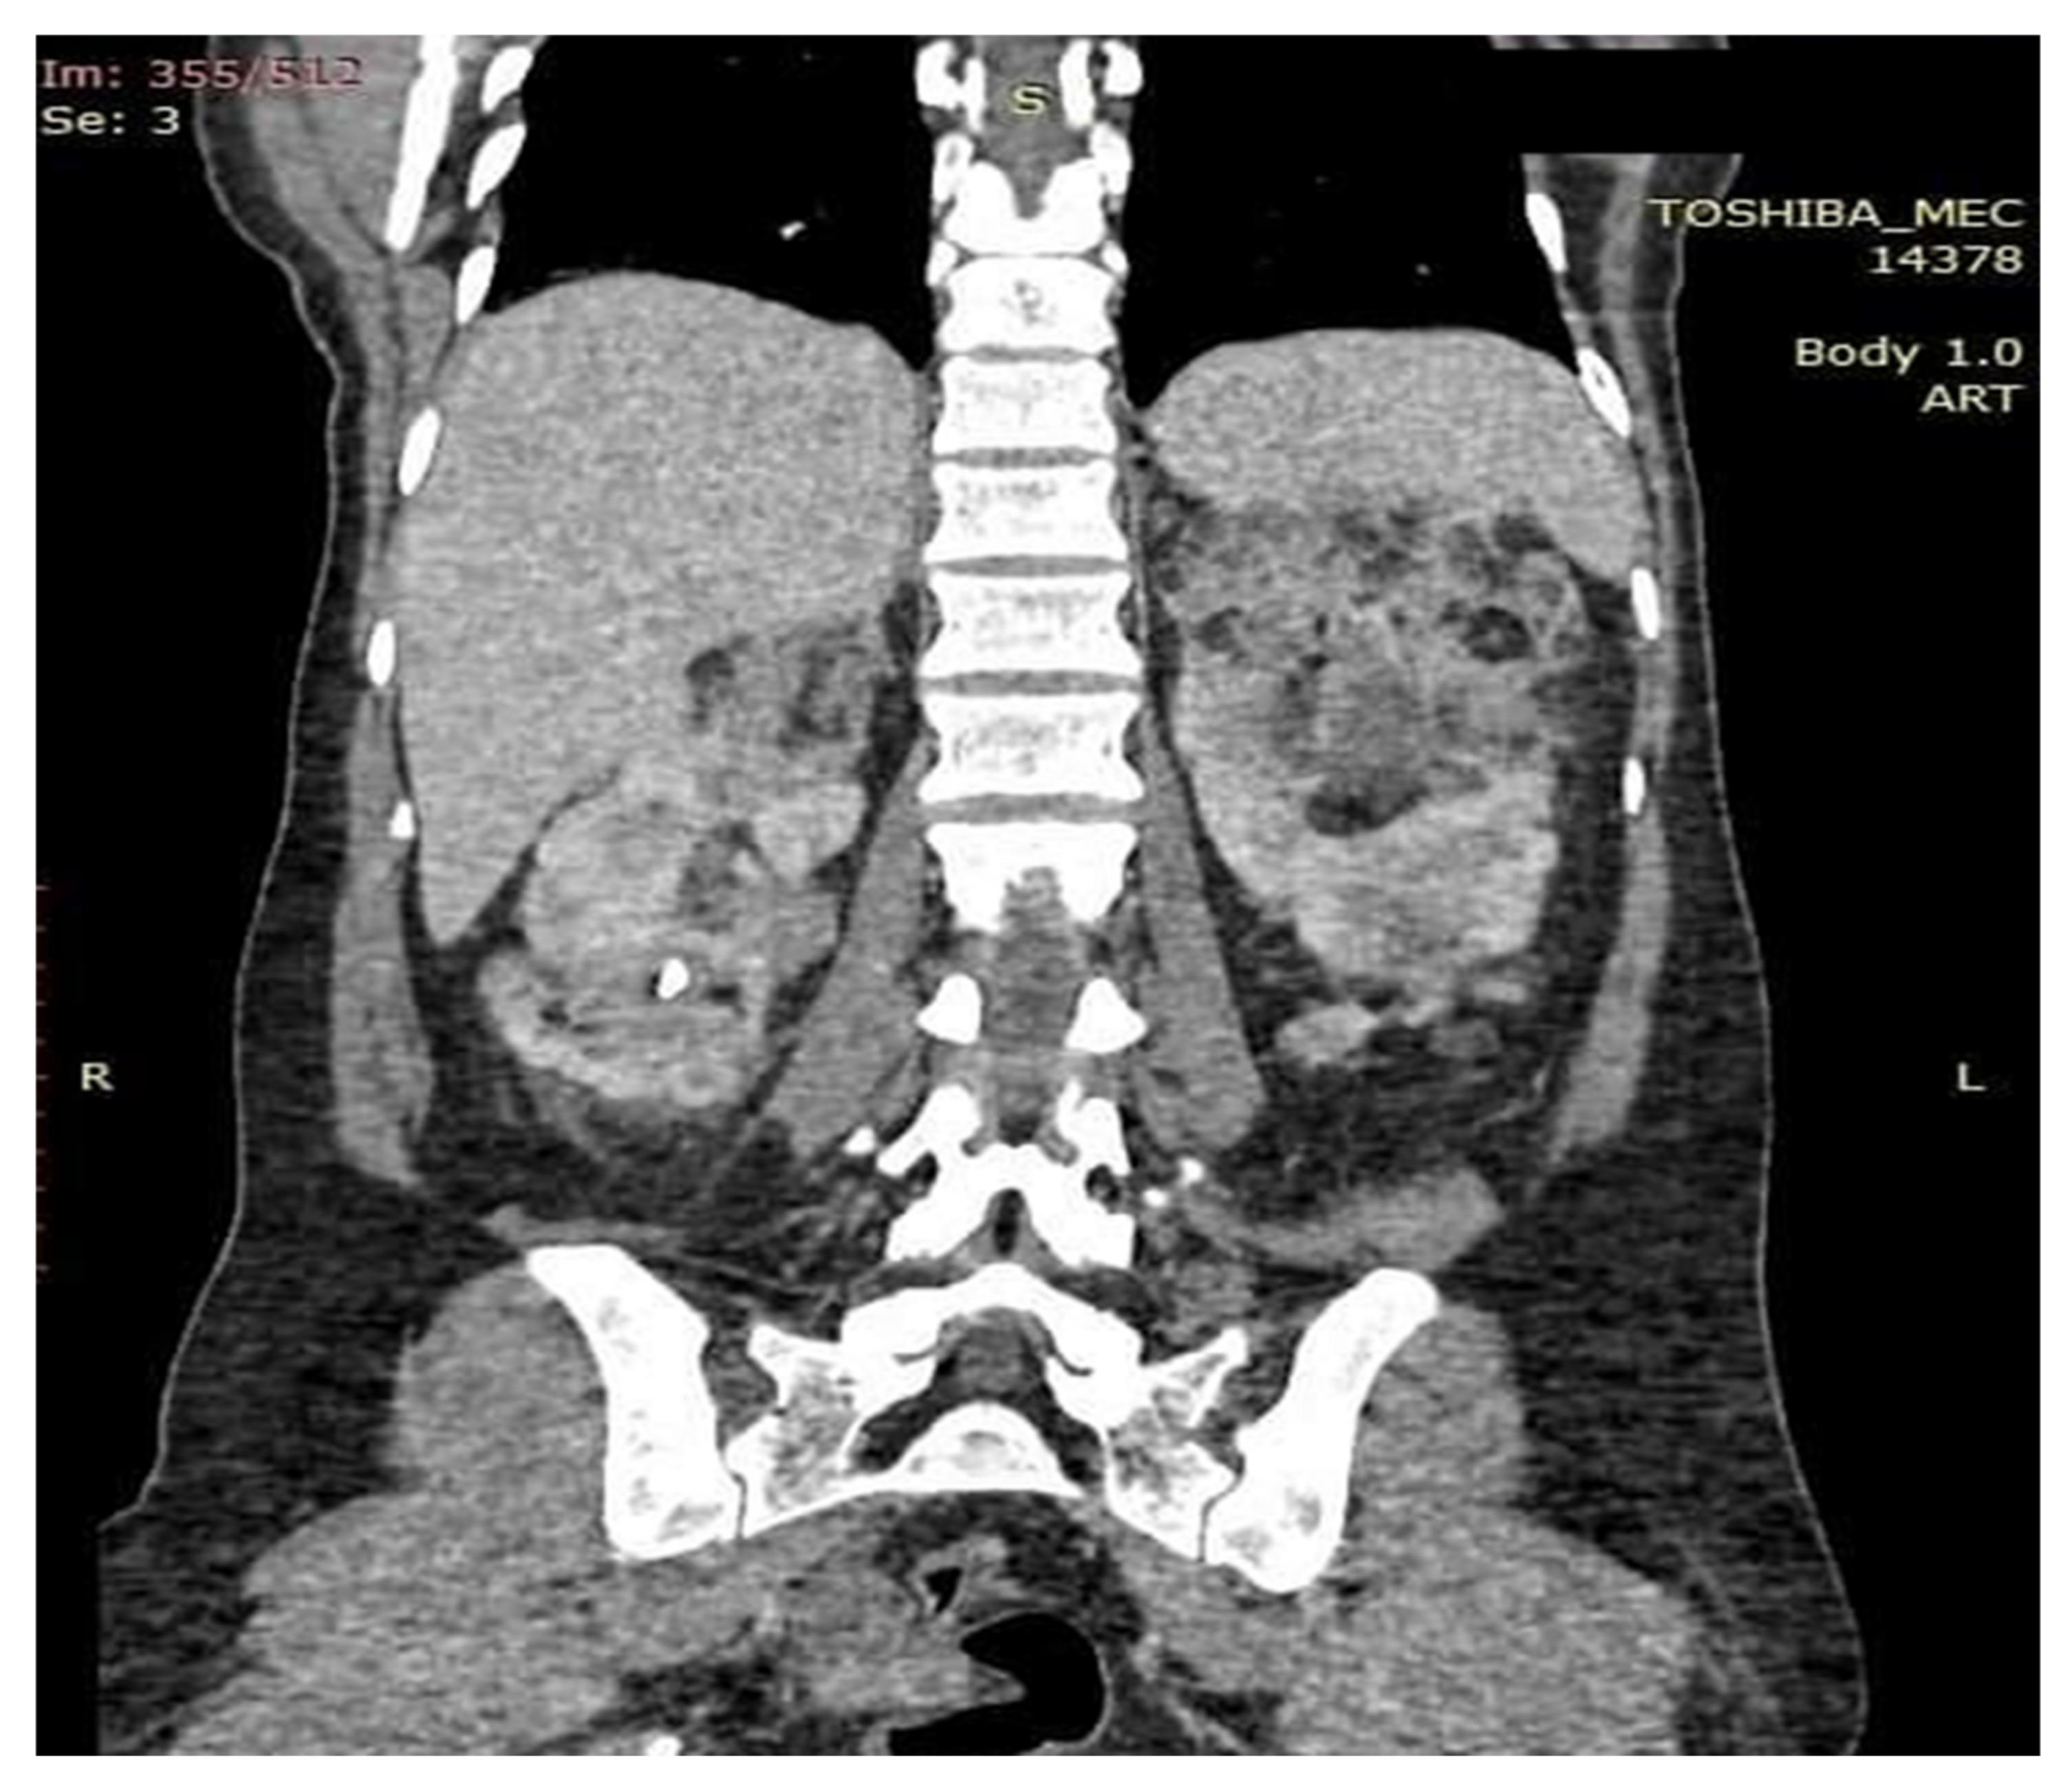

Figure 7.

Coronal section examination CT. Kidneys enlarged in volume with the same changes in shape and structure by the presence of angiomyolipomatous formations that deform the renal contours without causing infiltration of proximity structures.